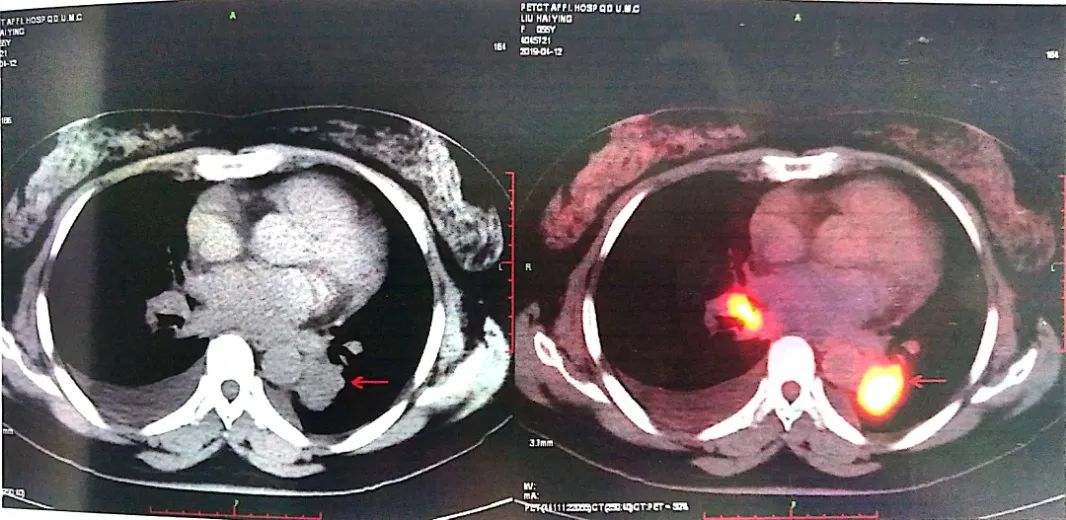

2019-04-12 PET-CT显示①右肺下叶后基底段胸膜下软组织密度肿块(大小26*30mm)。

②左肺下叶纵隔旁软组织密度肿块(大小28*31mm)。

③双肺门、纵隔内隆突下、气管旁、主肺动脉窗、血管前间隙、右侧颈部Ⅴ区及锁骨区多发增大淋巴结。

至此为止,患者的诊断为:肺恶性肿瘤 小细胞癌 广泛期 cT4N3M0 IIIC期(病灶1:右肺下叶,病灶2:左肺下叶),此时先给予标准化疗方案,EP方案:依托泊苷100mg/㎡ d1-3+顺铂75mg/㎡ d1-2 q21d*2。结果如下: